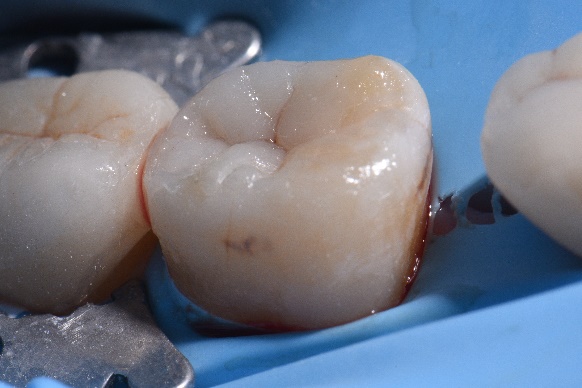

S-a îndepărtat sistemul de matrice înainte de realizarea stratificării estetice ocluzale, unde s-a utilizat GrandioSO (A2 shade, VOCO) (fig. 3-7).

Fig. 5 După îndepărtarea sistemului de matrice, s-a realizat restaurarea ocluzală (GrandioSO, A2, VOCO GmbH). |

Fig. 6 Restaurarea finală. |

Fig. 7 Aspect final după finisarea și lustruirea restaurării.